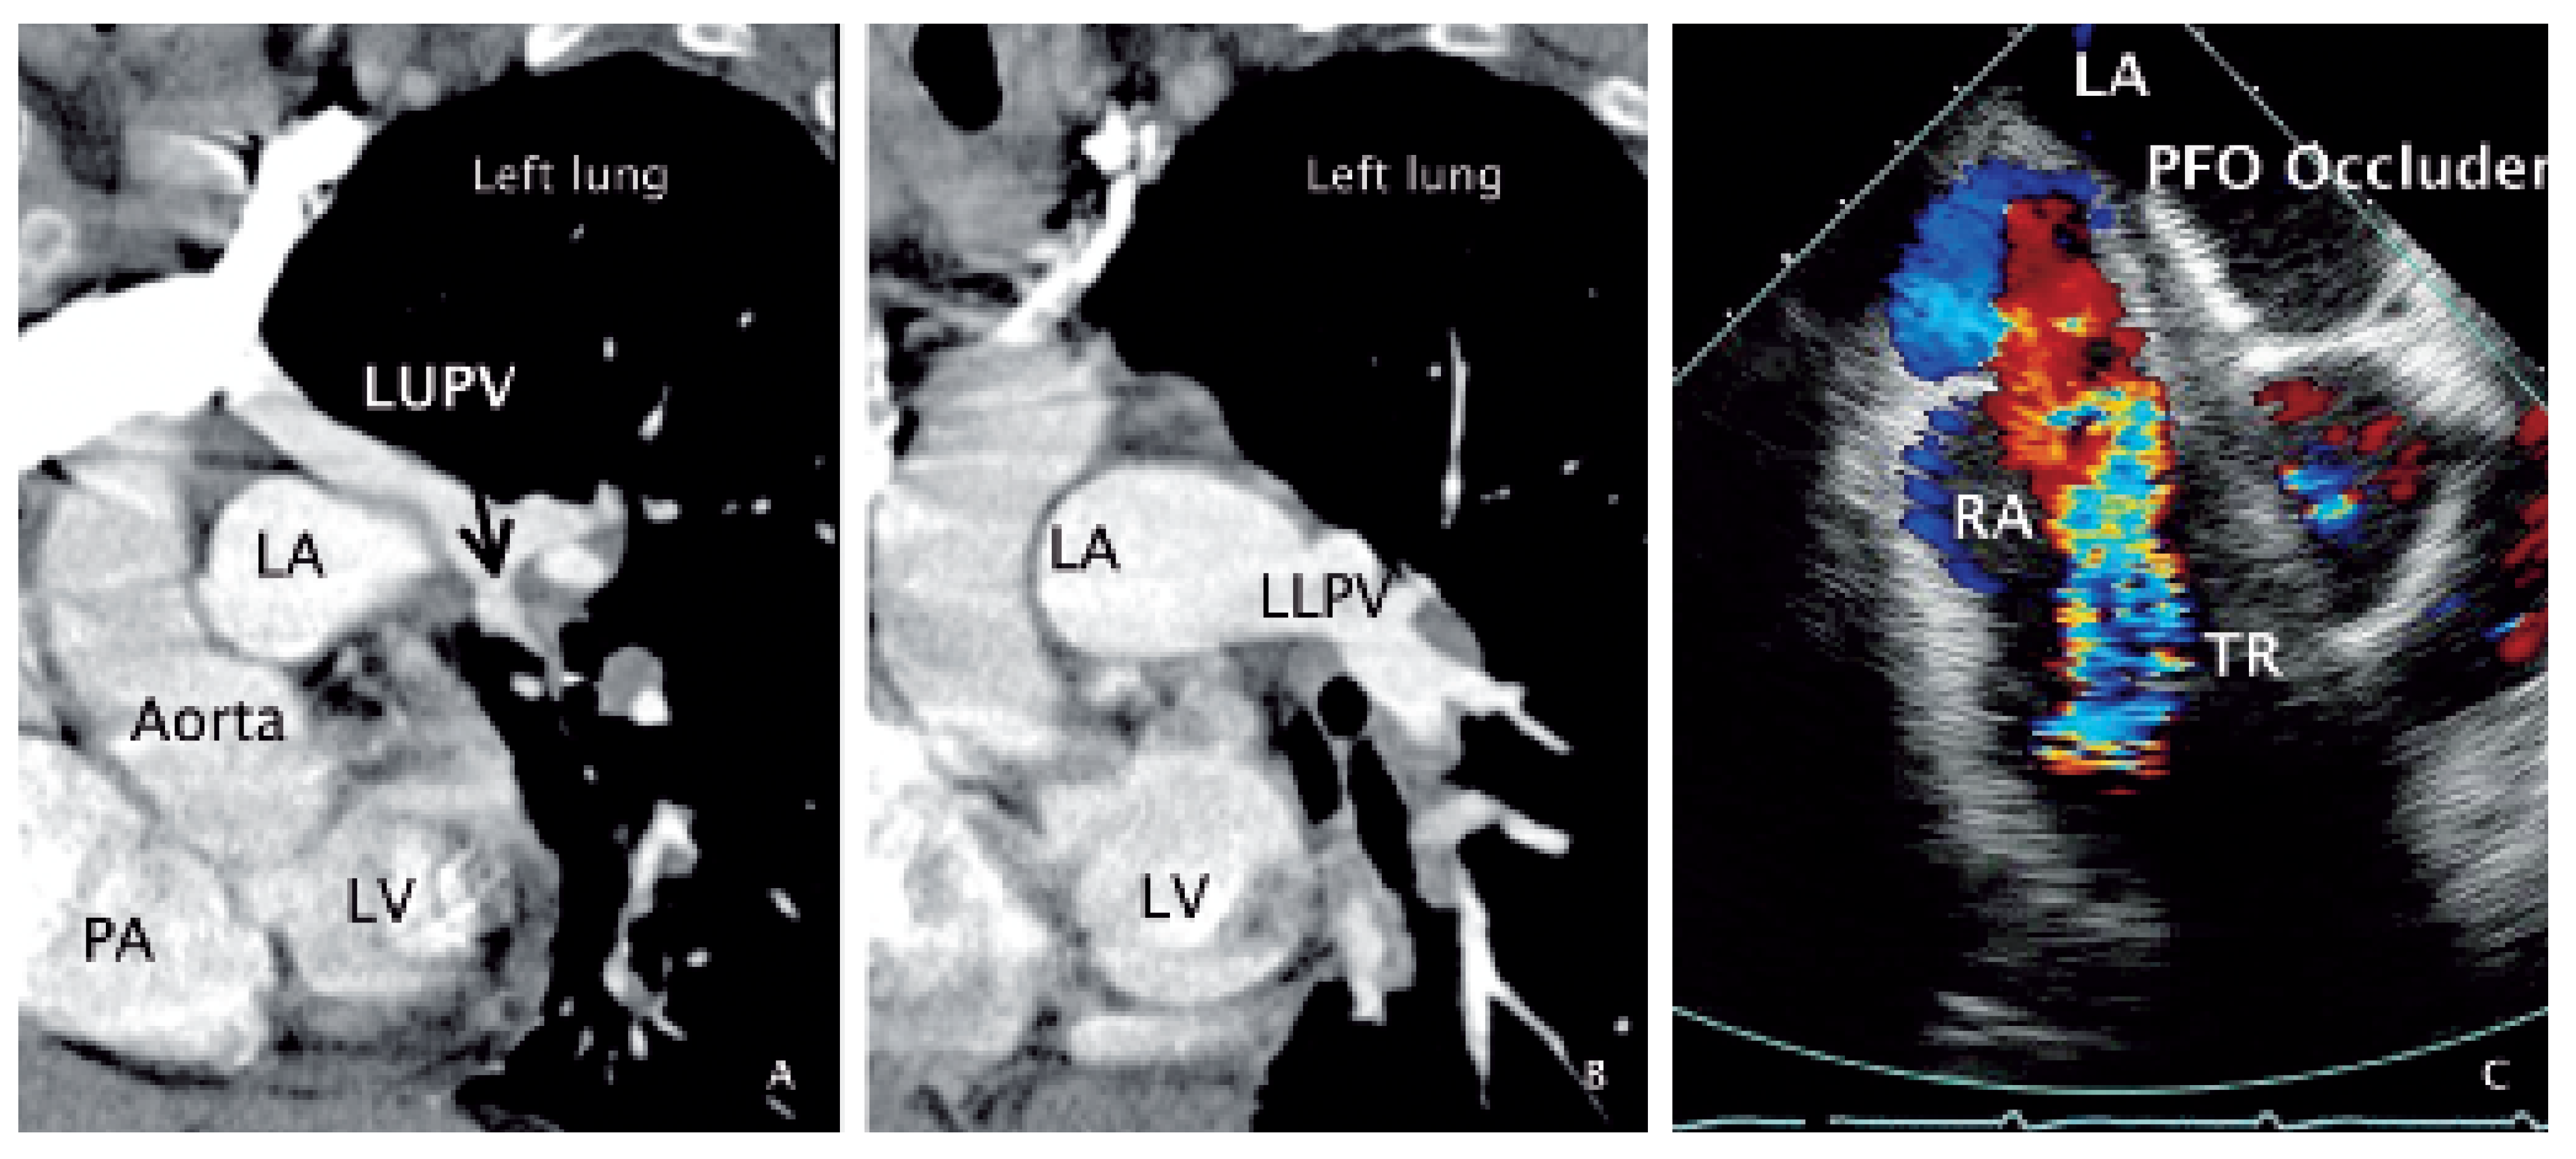

A 68-year-old woman was admitted for rapidly progressive systemic sclerosis. She suffered from exertional dyspnea and decreased exercise tolerance. Pulmonary function testing showed mild restriction with pulmonary fibrosis on high resolution computer tomography (CT). Dilatation of the right ventricle (RV) and right atrium (RA) ( Figure 1 A) with severe tricuspid regurgitation (TR) was detected by transthoracic echocardiography. Transoesophageal echocardiography was performed in search for intra-cardiac shunts, whereby the right upper (RUPV) and right lower pulmonary vein (RLPV) could be depicted ( Figure 1 B). Of the left pulmonary veins, only the left lower (LLPV) could be suspected to drain into the left atrium (LA) ( Figure 1 C,D), and no connection between the left upper pulmonary vein (LUPV) and the LA superior to the left atrial appendage (LAA) (arrowheads on Figure 1 D) could be imaged. Additionally, a large patent foramen ovale with spontaneous right-to-left shunt was found (PFO) ( Figure 1 B). Using angiographic CT, false drainage of the left upper pulmonary vein (LUPV) ( Figure 2 A,B) via the brachiocephalic vein into the superior vena cava could be shown. Cardiac catheterisation revealed normal coronary arteries and normal pulmonary artery pressure. In the context of a slight cyanosis (arterial oxygen saturation of 82%), and keeping in mind the possibly relevant function of the PFO as a release valve for the right heart volume overload (false pulmonary vein connection with secondary tricuspid regurgitation), it was closed transcutaneously by a 35 mm Amplatzer device ( Figure 2 C). The patient was dismissed in good clinical condition.

Figure 2. Angiographic computed tomography and transoesophageal echocardiography. A Oblique section through the LV, PA, aorta andLA imaging the LUPV (arrow) as it does not drain into the LA, but is located alongside the lateral LA wall, and connects to a big vessel in the upper left partof the panel (brachiocephalic vein). B Oblique section at identical angle as in panel A but taken at a slightly more caudal position depicting the LLPV and its drainage into the LA. C Transversal (30°) plane colour Doppler view showing the LA and RA with the implanted PFO occluder to the left and right of the inter-atrial septum, a cross-section through the aortic root an the extensive and turbulent flow velocity signal of the severe tricuspid regurgitation.LV = left ventricle; LA = left atrium; PA = pulmonary artery trunk; LUPV = left upper pulmonary vein; LLPV = left lower pulmonary vein; RA = right atrium;PFO = patent foramen ovale; TR = tricuspid regurgitation